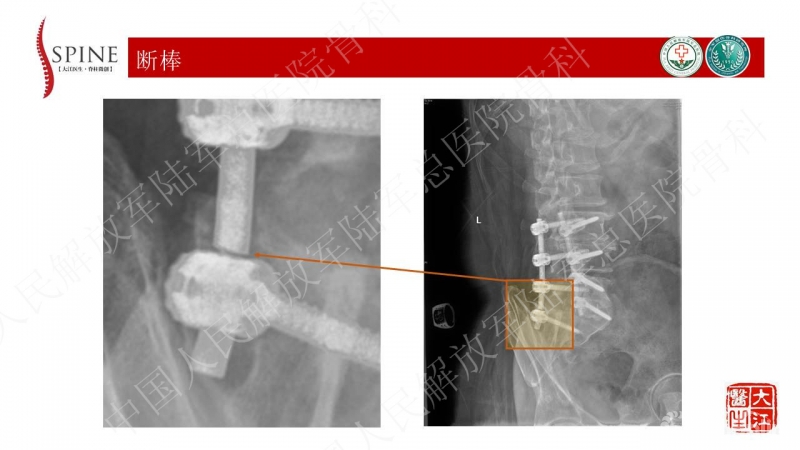

患者主诉为腰痛伴下肢疼痛,腰痛为主,翻身活动、下地时疼痛加重。体格检查也为下腰段的叩压痛,影像可见腰5-骶1断棒。断棒的原因都是力学应力相关的原因,而患者SVA(矢状位垂直轴)不大,全身平衡状态尚可。结合CT表现,应怀疑腰5-骶1节段未融合。

本病例的焦点在患者腰痛的原因,患者明确其腰痛非慢性腰痛,伤后出现。结合病史、体格检查、断棒的表现,主要考虑下腰段的原因。要考虑两个原因,一是腰5-骶1的未融合,断棒后不稳,局部应力集中。二是断棒后局部异常活动,带动瘢痕牵拉硬膜囊及神经根的向背侧牵拉,这种异常活动在残留小关节的抵挡下会引起严重卡压,而出现下肢的疼痛、甚至神经功能损害等。患者行原术区内固定取出,腰5-骶1内固定术,术后取得良好效果,证实患者本次疼痛病因为腰5-骶1节段断棒后应力集中、异常活动。